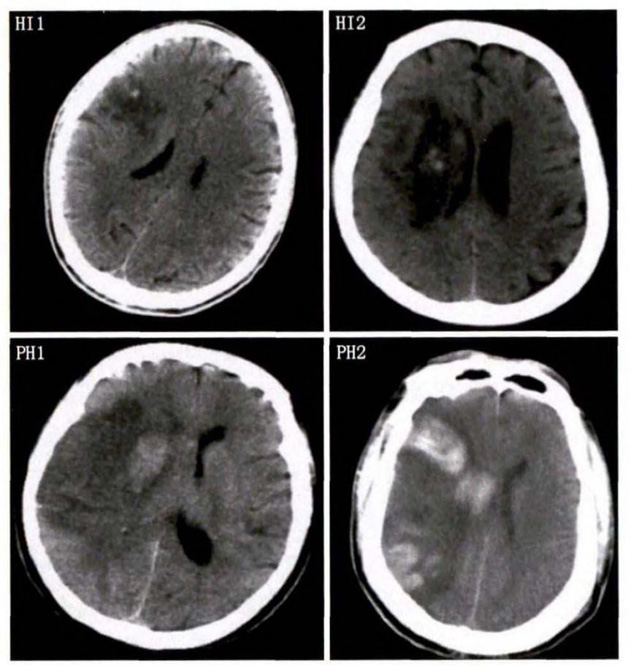

中、老年病患,有動脈粥樣硬化及高血壓病等腦卒中的危險因素,發病結合神經系統癥狀和體征,應當考慮急性腦梗死的可能。再經腦CT/MRI發現梗死灶,或排除腦出血、炎癥性疾病等,診斷即可確定。腦梗死有時頗似小量腦出血的臨床表現。腦栓塞在任何年齡都可以有發病的風險,可以在幾秒到幾分鐘達到頂峰。會有偏癱不能說話等局部神經功能損壞。栓子來源很種,可能是冠心病、心肌梗塞、心內膜炎等。合并心房纖顫,結合其他臟器官的支持診斷,CT跟磁共振都可以檢查確定栓塞位置數量還有是不是有伴發出血等問題??梢詭椭\斷。

中老年有高血壓糖尿病發病病史,起病神經功能缺損癥狀,臨床表現為腔隙綜合征,即可初步診斷本病。如果CT或磁共振證實有與神經功能缺失一致的腦部腔隙病灶, 符合大腦半球或腦干深部的小穿通動脈病變,即可明確診斷。少數患者隱匿起病,無明顯臨床癥狀,在影像學檢查時發現。